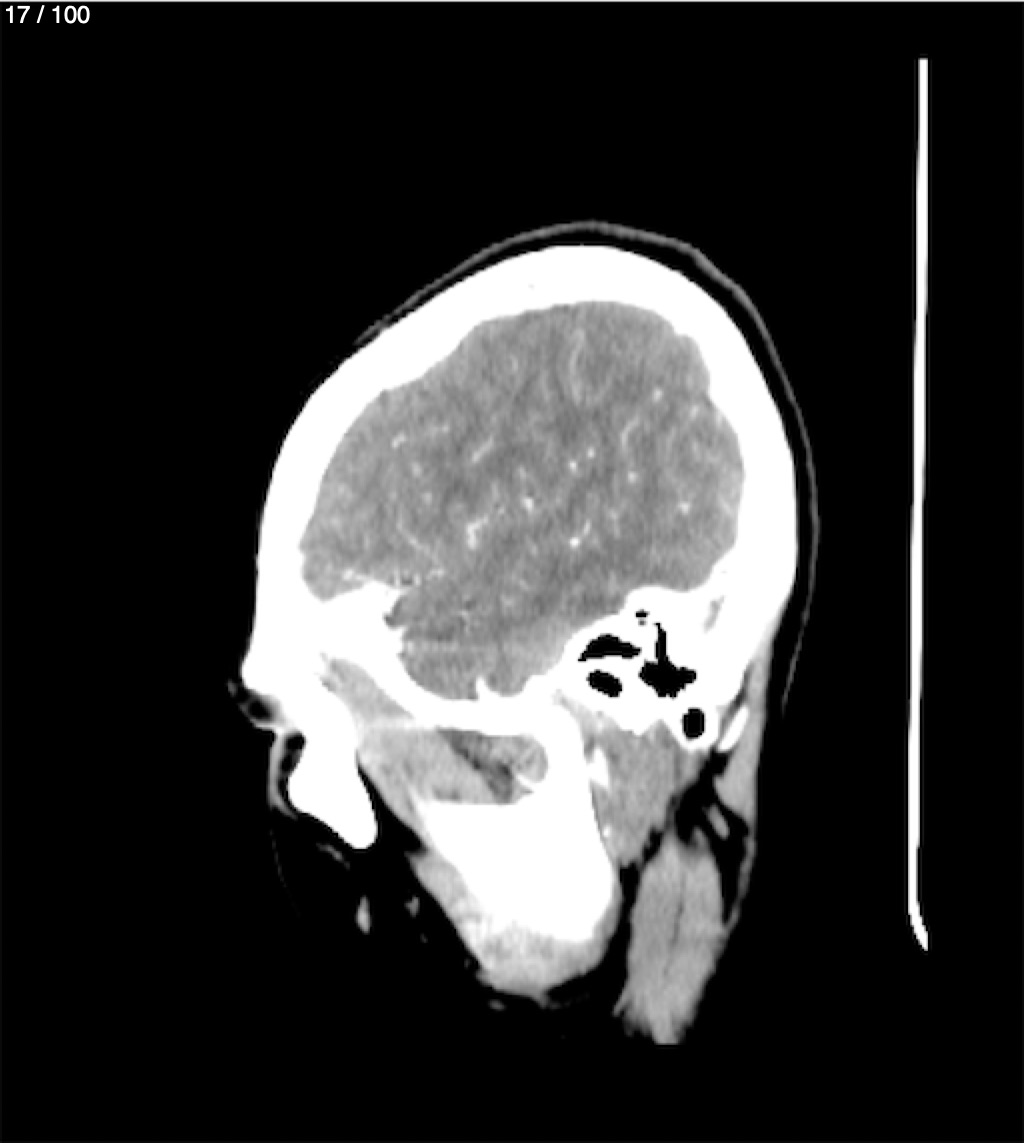

Fernando Daniel Gutierrez Caraba - Tc. Craneo Syc